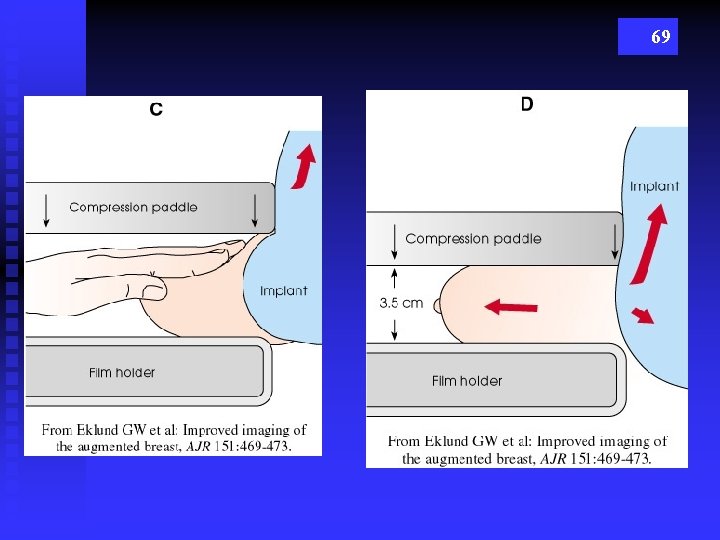

68 “PUSH BACK” TECHNIQUE

69